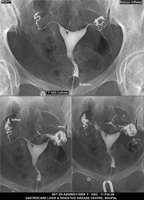

Section: HSG

Total: 49 Cases

All Categories BaM Enteroclysis Loopogram BaE Fistulogram Urethrogram HSG